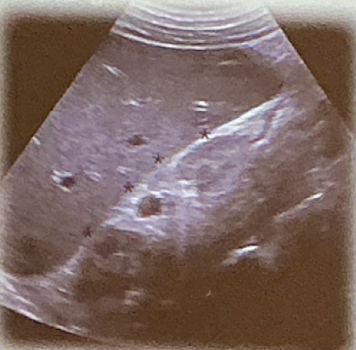

2. Cuadrante superior derecho (ventana hepatorrenal )

Evaluamos: Hígado, riñon derecho y espacio hepatorrenal (fondo de saco de Morrison).

Tambien vesicula y diafragma